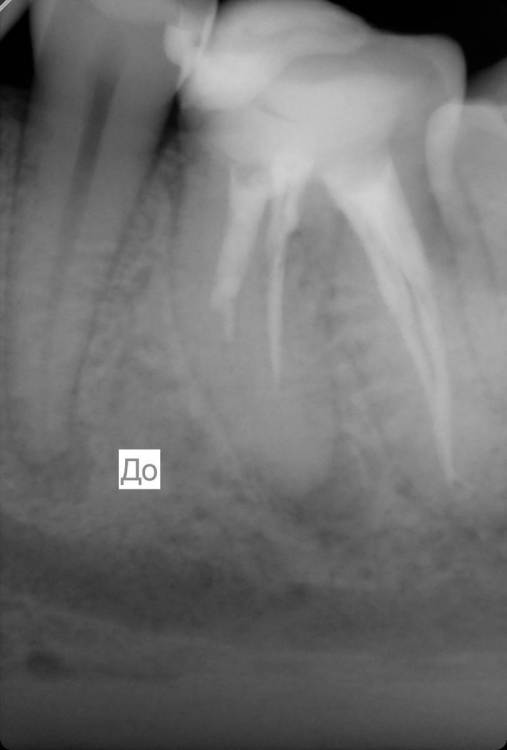

chacraborti Опубликовано 13 февраля, 2024 Поделиться Опубликовано 13 февраля, 2024 Делали ре-ендо зуба 36, прошел год прикрепляю снимок до и после. Прошло ли воспаление у верхушки корня? Ссылка на комментарий